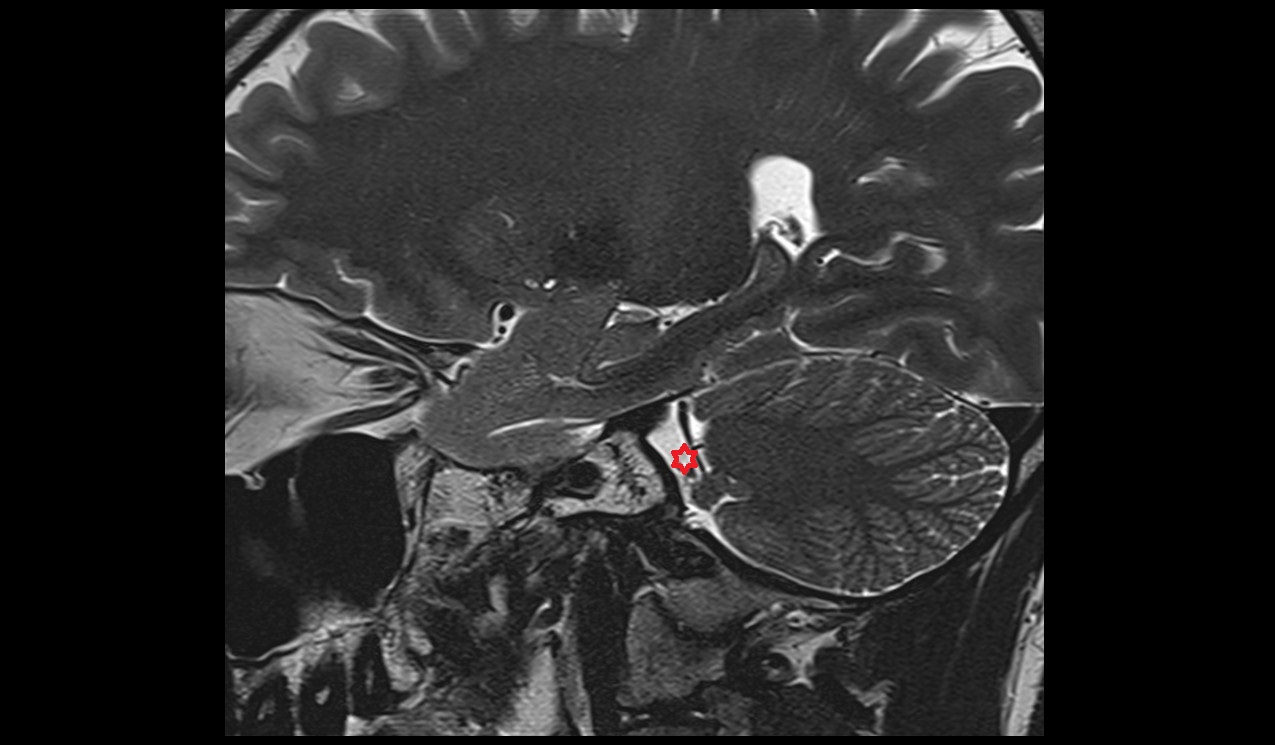

- Median aperture of fourth ventricle (foramen of Magendie)